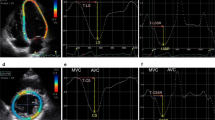

A commercially available speckle-tracking echocardiographic software program (EchoInsight, Epsilon, Ann Arbor, MI) was used to obtain 2D strain data from DICOM-format images offline for all included patients. EchoInsight software derives strain values using natural strain algorithms. Right ventricular longitudinal strain data were prospectively extracted in a blinded manner from images acquired in the four (4C) chamber view. A point-and-click approach was utilized to identify 3 RV anchor points (both annuli and RV apex) enabling the software to track the endocardial contour automatically. Subsequently, tracking was visually inspected throughout systole to ensure adequate border detection and the endocardial contours adjusted manually as necessary to further optimize tracking. Segments identified as inadequate for strain analysis by the software were noted. Longitudinal strains for each individual segment were measured and averaged to obtain RV septal (basal mid and apical walls) and lateral RV free wall (basal, mid and apical) strain. RV global longitudinal strain (GLS) was estimated by averaging septal and lateral right ventricular segmental strains (Fig. 1).

No significant differences in fractional area change (%) and RV systolic pressure among studied groups were found. RV fractional area change was comparable in all 3 groups, while right ventricular tricuspid annulus systolic excursion was not significantly different in patients with HCM compared with hypertensive subjects Table I). Right ventricular annular tissue Doppler S′ and E′ peak velocities were decreased in patients with HCM compared to all other groups. Adequate tracking and strain quantification was possible in 94 % of analyzed RV segments. Septal strain was attenuated in H-LVH compared to controls. RV global longitudinal strain (GLS), (as well as septal and lateral RV myocardial strain values) were significantly impaired in patients with HCM compared to patients with H-LVH, and controls (p < 0.001 for all comparisons) (Table 2).

To explore the discriminatory ability of various echo parameters to discern HCM from LVH, receiver–operator characteristic (ROC) curve analysis was performed. Optimal cut-off values for RV strain and echocardiographic parameters presented on Table 2, were determined by using the ROC curve. Global longitudinal strain provided the highest area under the curve (0.96 ± 0.02) for discriminating HCM. An RV GLS cut-off value of 14.9 % differentiated HCM and H-LVH with 90 % sensitivity and 95 % specificity (p < 0.001). 90.6 % of cases in the HCM had GLS less than the cutoff. None of the patient with HCM had normal GLS values. Regional and global RV strain parameters were not significantly different between H-LVH patients, and controls (Table 2).

Inter-observer and intra-observer agreement for strain parameter measurements was excellent for GLS. Intra-observer correlation coefficient was 0.97 [95 % confidence intervals (CI) 0.92–0.99, p < 0.001] and inter-observer correlation coefficient was 0.98 (95 % CI 0.97–0.99, p < 0.001). Bland–Altman analysis showed mean bias ± 2 SD of 0.29 ± 1.073 with 95 % limits of agreement −1.81 to 2.395 and 0.052 ± 0.77 (−1.45 to 1.56) respectively (Figs. 2a, b, 3).